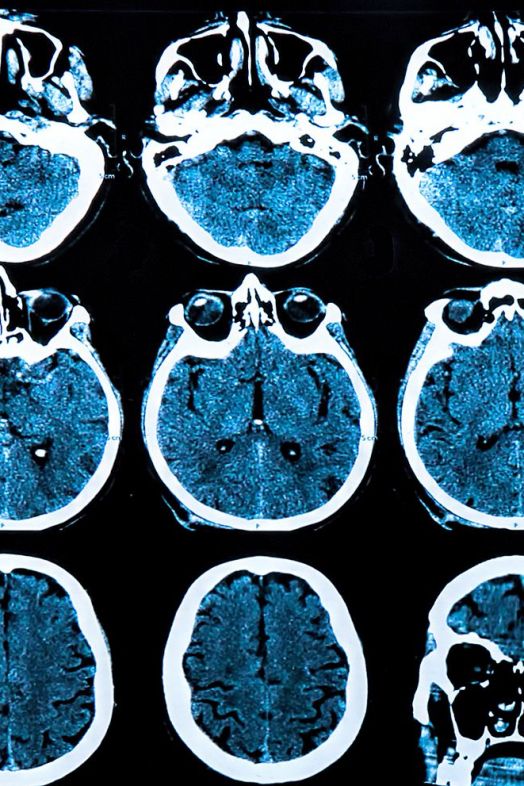

Las técnicas de imágenes neuronales objetivas, como la tomografía por emisión de positrones (PET), la resonancia magnética (MRI) y la ecografía Doppler transcraneal (TCD), brindan información estructural y funcional útil, pero tienen un valor limitado en el diagnóstico clínico de la EP debido a los procedimientos complejos, los largos tiempos de exploración y los altos costos. Por lo tanto, para brindar tratamientos precisos y oportunos para los pacientes existe una necesidad imperiosa de una solución de diagnóstico objetiva que sea fácil de operar, rápida de escanear y de bajo costo.